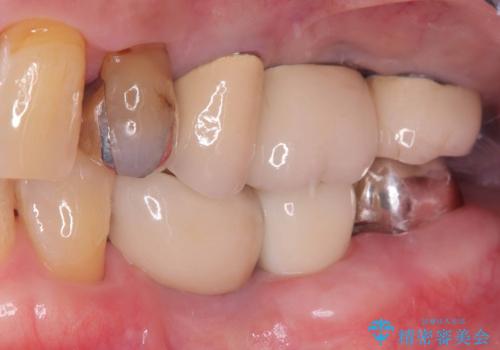

- 「歯を咬むと痛い」を主訴に来院された患者様です。 CTを撮ると歯根が縦に真っ二つに割れている状態で、歯周ポケットも10㎜を超える状態でした。

歯の保存は困難と診断しインプラントで治療を行いました。1Dayインプラントの適応だったので、抜歯した当日にインプラントを埋入しました。